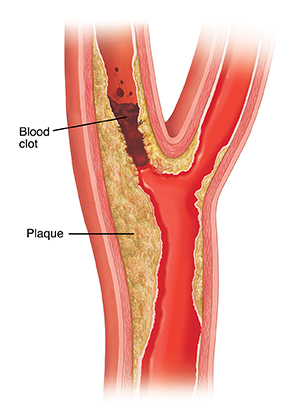

Clots form

When blood pressure is too high, it can damage blood vessel walls and create scar tissue. Fat and cholesterol (plaque) collect in the damaged spots. Blood cells stick to the plaque, forming a mass called a clot. A clot can block blood flow in the vessel.